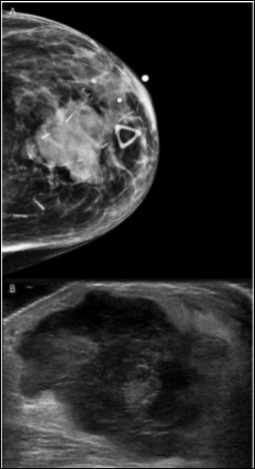

We report the case of a breast melanoma in a 75-year-old woman with a cancer history significant for ampullary adenocarcinoma for which she underwent surgery and chemoradiation approximately 9 years earlier. She presented to her oncologist with a left breast lump which appeared suddenly. There was no axillary lymphadenopathy. Diagnostic ultrasound and mammography revealed a 3.3 cm solid mass at 12 o’clock deep to the areola which approached the skin (Figure 1). Fine needle aspiration was performed at that time which was positive for malignant cells, consistent with a high grade sarcoma or spindle cell type carcinoma (Figure 2A,B). The malignant cells were focally positive for GATA3 and negative for ER and PR, and this was thought to represent a primary breast cancer. A metastasis from her ampullary adenocarcinoma was ruled out immunophenotypically. The patient chose to undergo mastectomy for definitive diagnosis and treatment.

Figure 1.Radiological Findings. Radiographic imaging of the breast revealed a heterogeneous, hypoechoic solid mass with vascularity measuring 3.3 cm with associated thickening of the skin. A. Tomography, B. Ultrasound